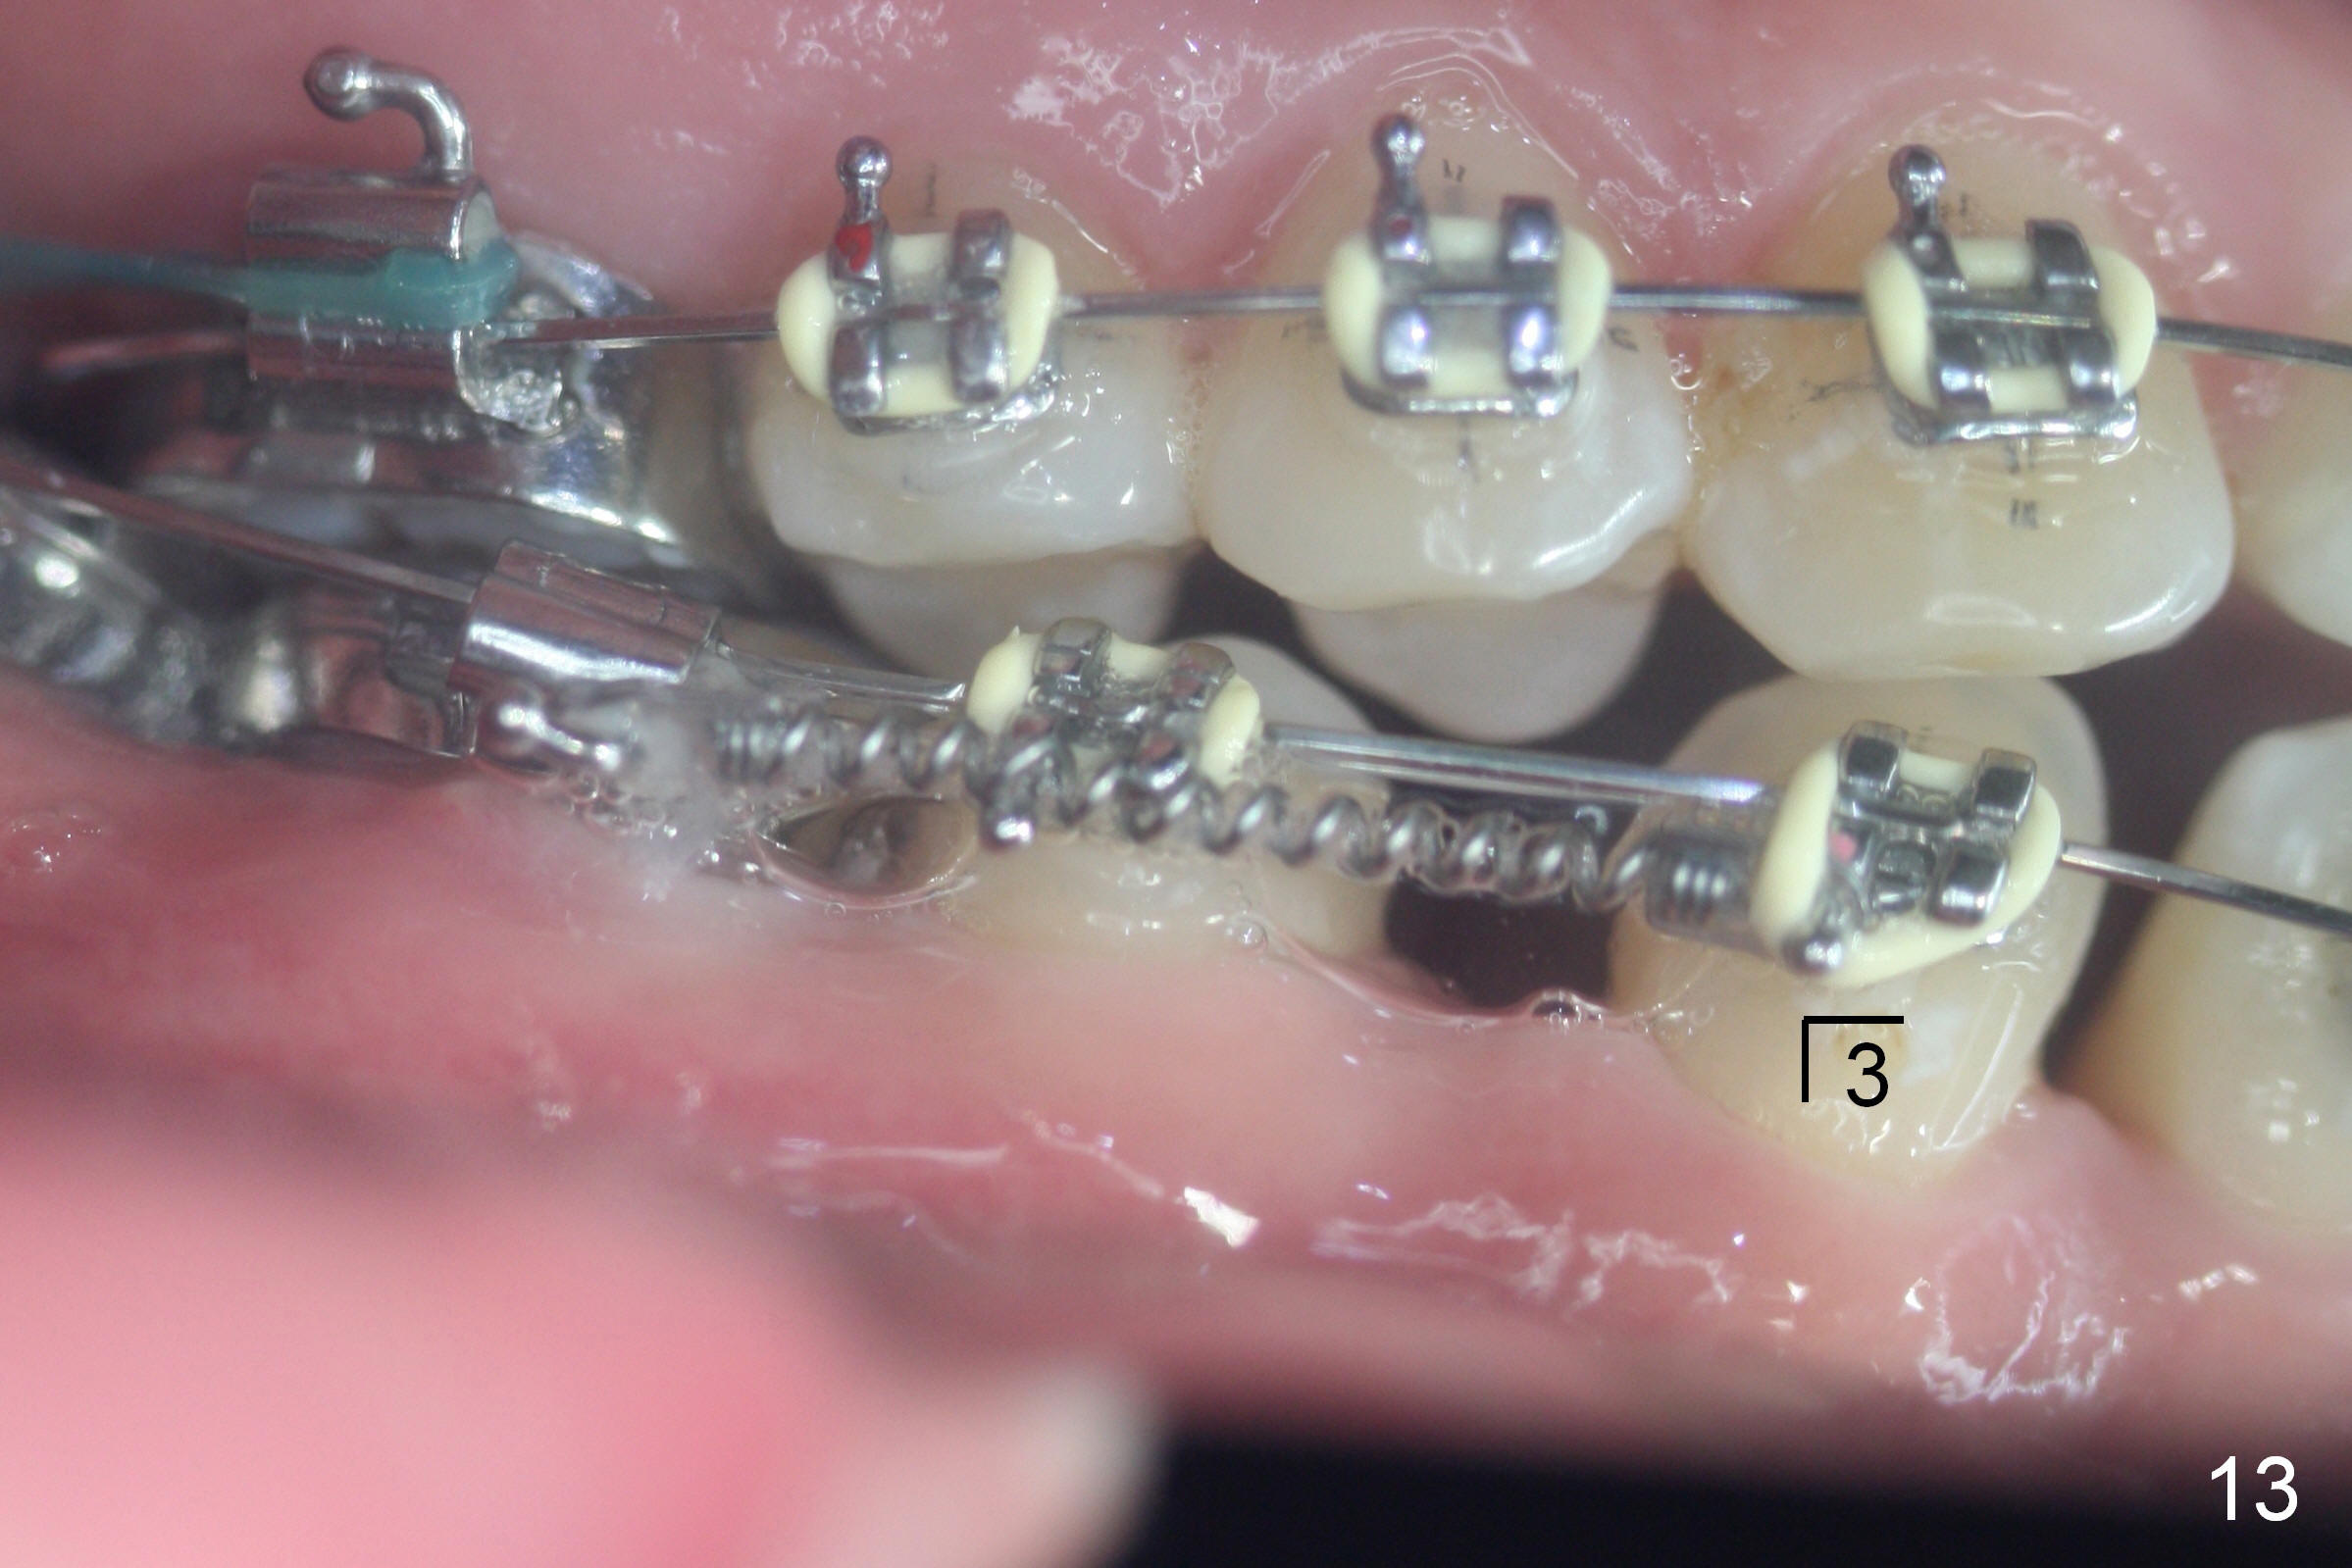

Four months post bracketing, two of 8 mm Ancor Mini-implants are placed at the sites of the upper 2nd molars and power chain of 3 placed between the 1st molars and the mini-implants (Fig.6,8). Niti Closing Springs (12 mm and 9 mm) are placed between LR4 and 7 and LL 3 and 6, respectively (Fig.7,9, 16x16 ss wires). The forces are 100 and 150 mg, respectively.

Two weeks later, it appears that U3s do not move distal (Fig.10,12), whereas the lower teeth do (Fig.11,13). Power chains change to 2 with grey ones. If no more change occurs in 1 week, change to next wires with power chains x 4 with one end attached to the lingual cleat (Fig.10,12 arrowheads) so that U3s may evenly (buccal and palatal) move distal. If LL3 keeps moving much faster than LR4, switch the closed coil springs.